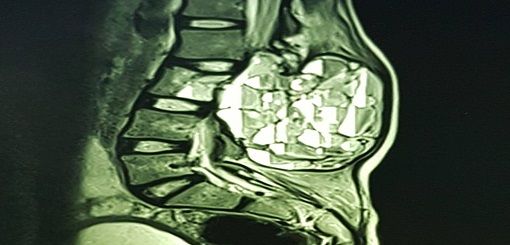

Se realizó una cirugía de columna de alta complejidad a niña de 13 años